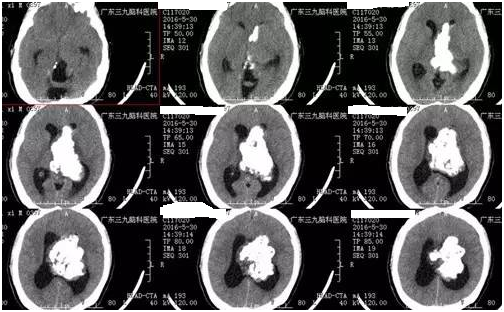

陈男子,39岁,3个月前开始头晕头痛,在卫生院抓药吃后有所缓解,近1个月症状加重伴恶心、呕吐、肢体乏力,为求进一步治疗来我院就诊。入院后完善相关检查,提示:肿瘤位于脑室内,钙化明显,形态不规则,肿瘤最大径8.1cm,双脑室不同程度扩大,诊断:双侧侧脑室巨大占位性病变;梗阻性脑积水。由神经外一科张良教授主刀切除脑室内肿瘤,解除脑积水,经系统康复治疗后,患者症状缓解出院。术后病理提示中枢神经细胞瘤,WHO II级。

▲术前CT